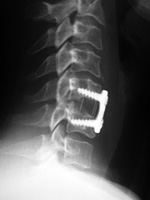

Anterior cervical disk fusion (ACDF) cage at C5-6 Occipital strut with posterior cervical plates Posterior cervical spine clamp Odontoid fracture fixation

Posterior cervical spinal clamp Odontoid fracture fixation

The disk cage is probably composed of PEEK.   Patient with rheumatoid arthritis and atlantoaxial (C1-C2) subluxation and generalized cervical spine laxity Postoperative lateral radiograph of the cervical spine. There is fixation of an odontoid base fracture by an odontoid screw and a sublaminar wire between C1 and C2. There are also skin staples and a surgical drain in the posterior aspect of the neck.